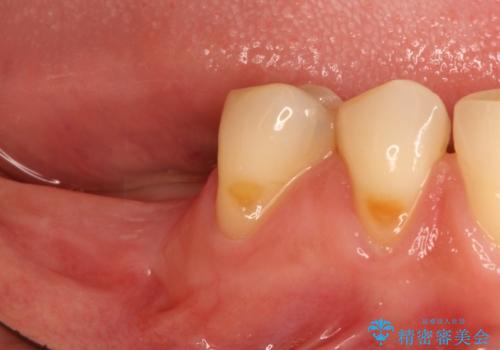

奥歯が痛い。抜歯~奥歯のインプラント

- 30代女性

- 奥歯が破折していたため、抜歯を行ったあとインプラントを埋入して咬合回復を行っております。